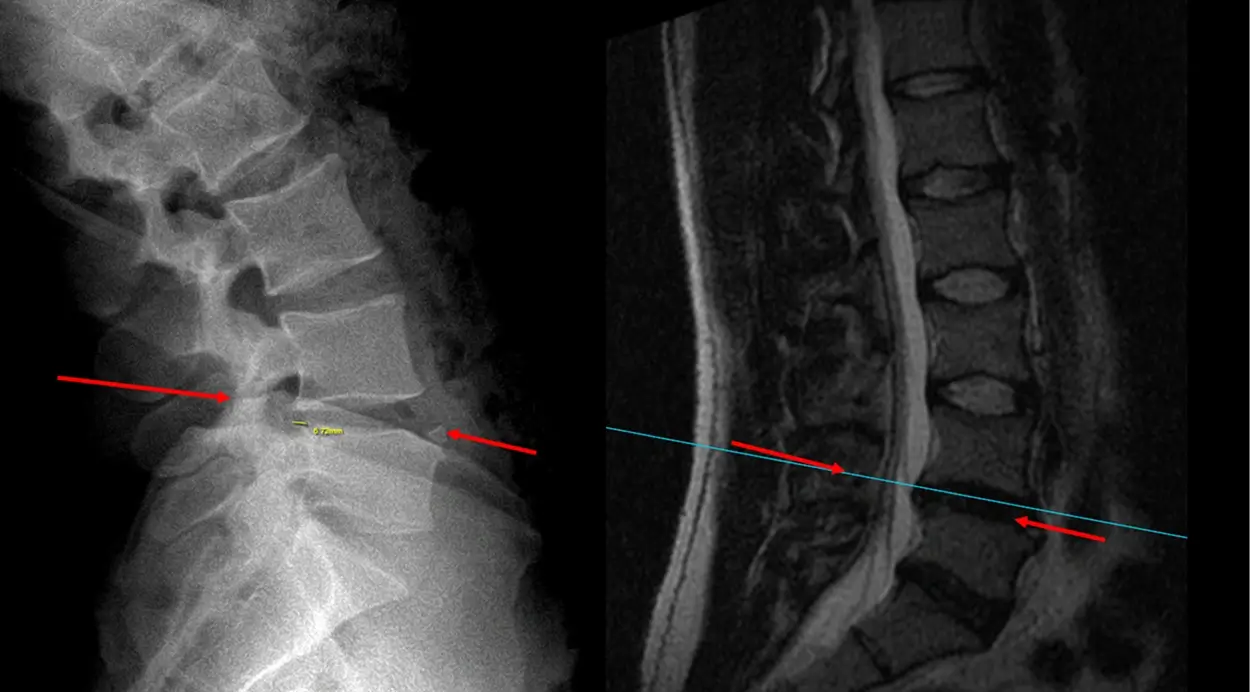

Pre OP radiographs, frontal and sagittal views

Pre OP MRI and radiograph sagittal view